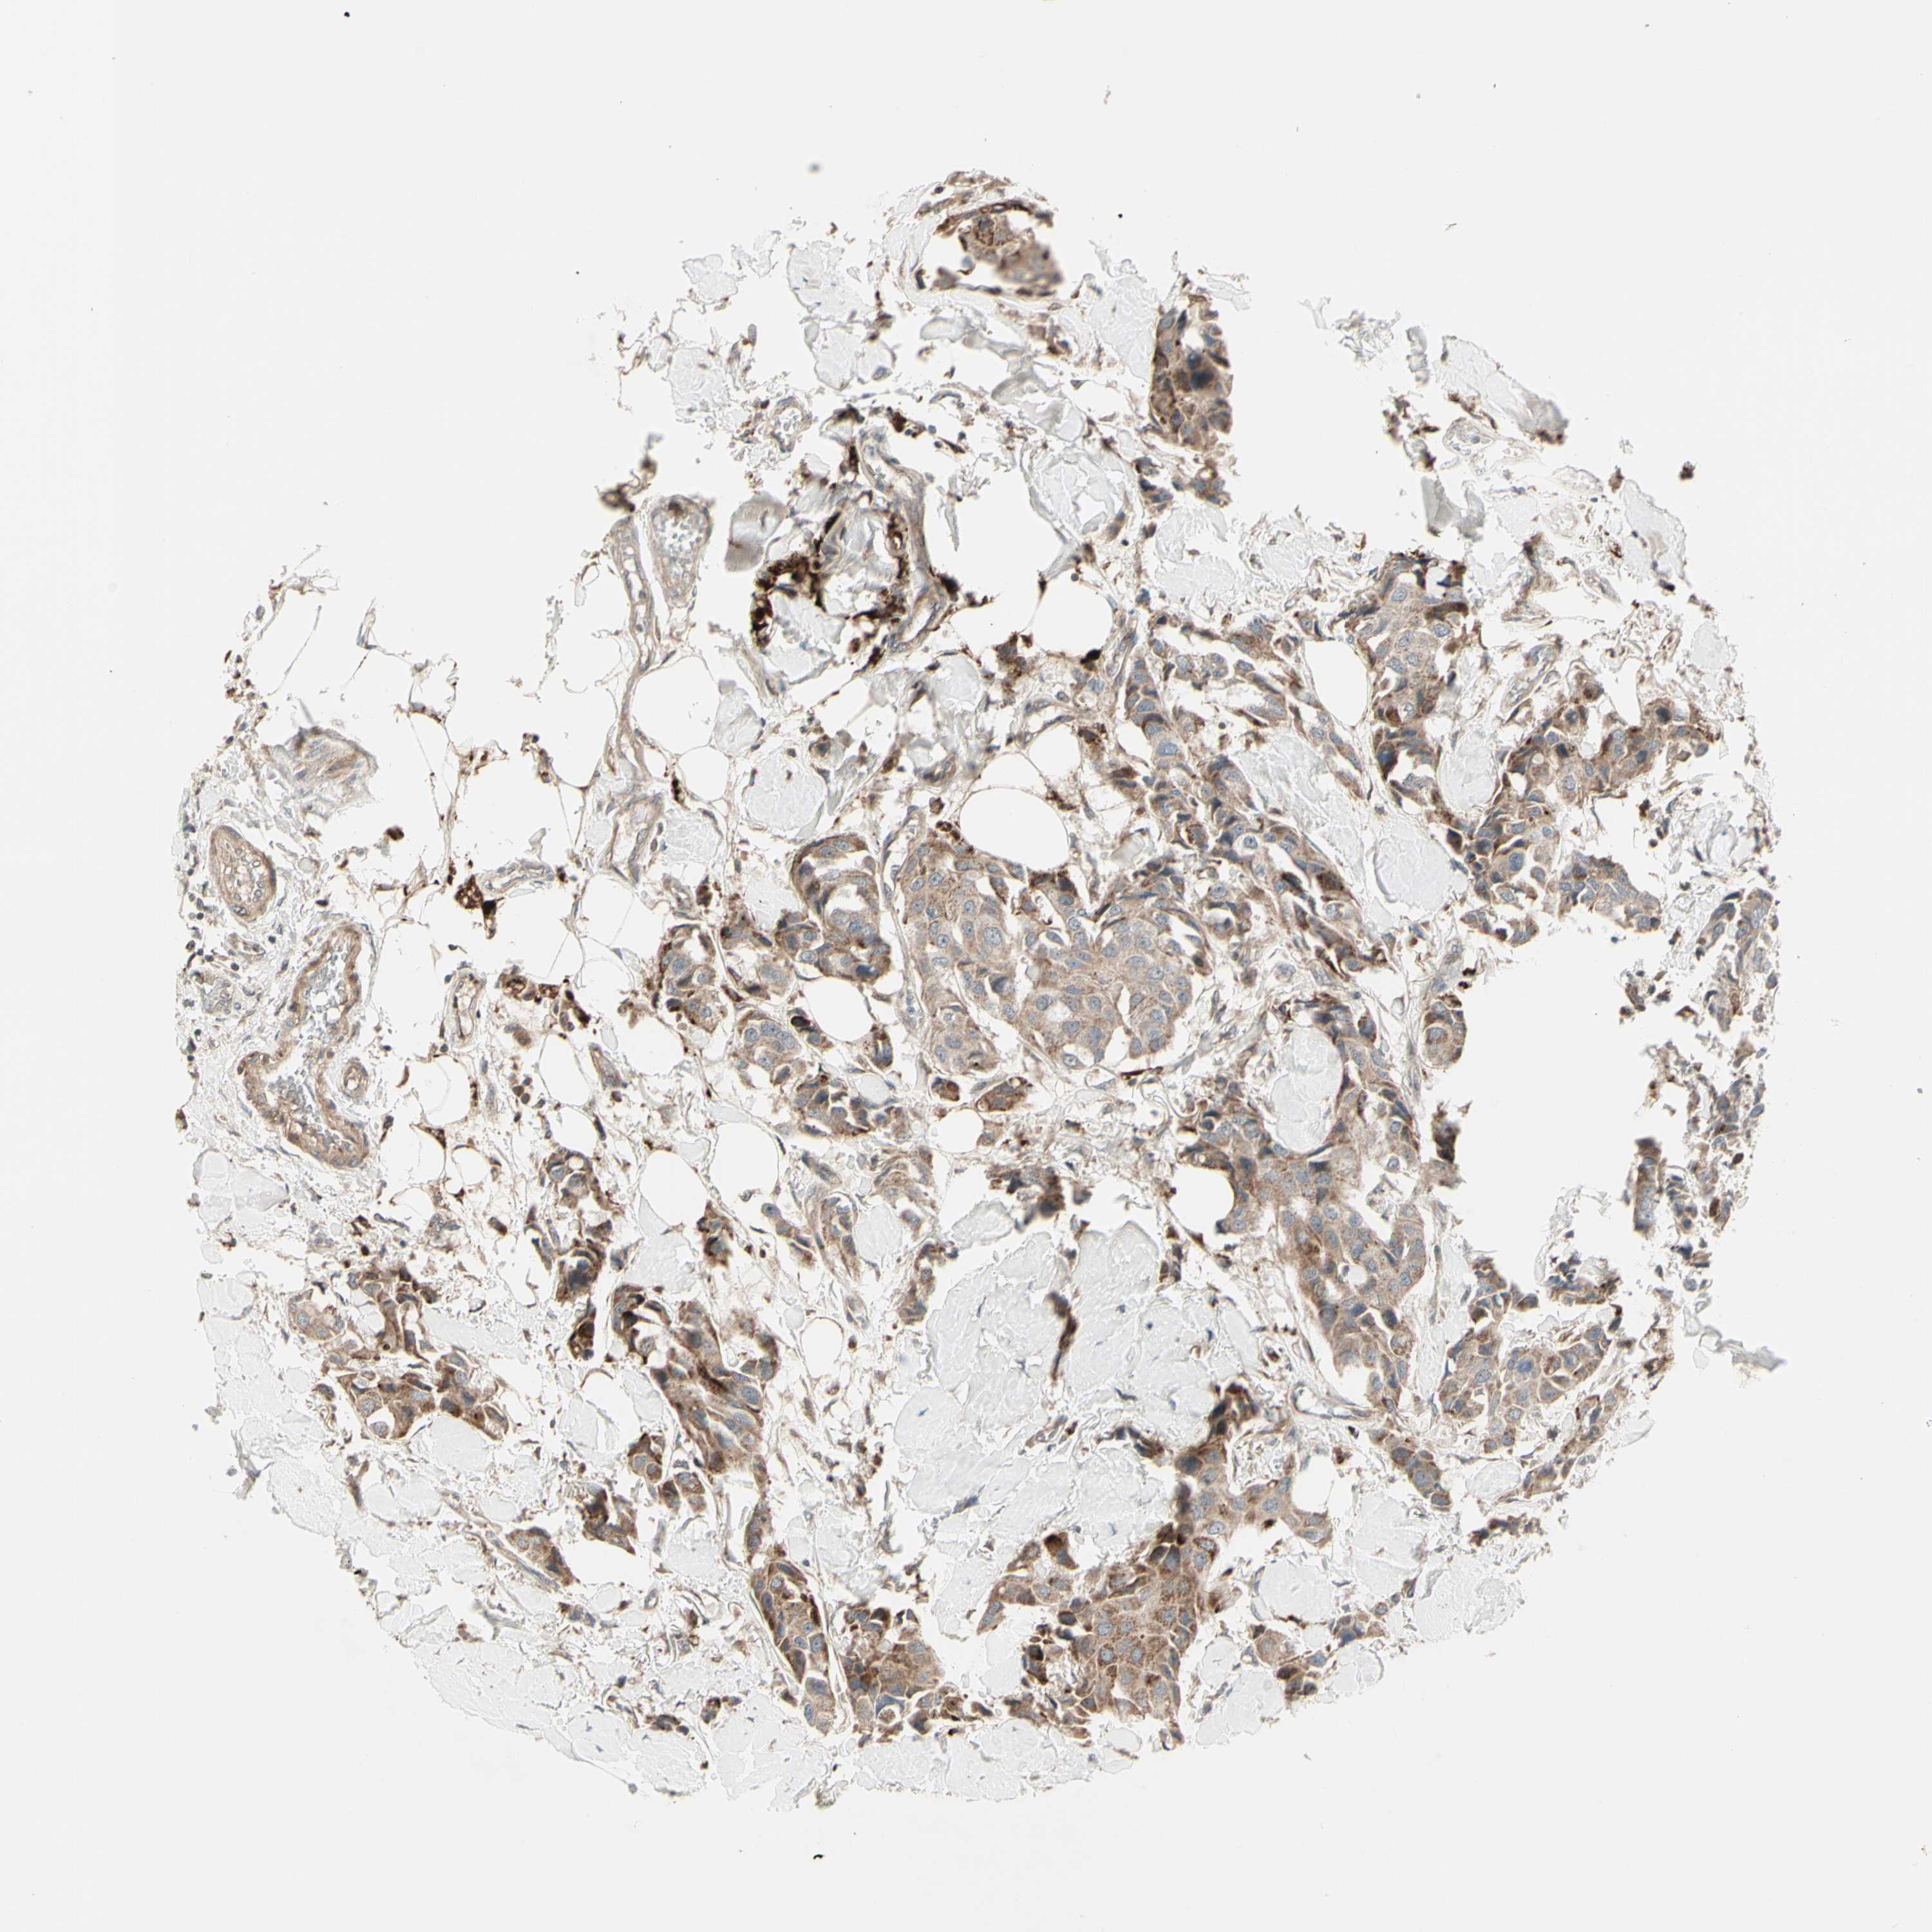

CANCER BREAST CANCER Show tissue menu

BRCA TCGA BRCA VALIDATION PROTEIN EXPRESSION